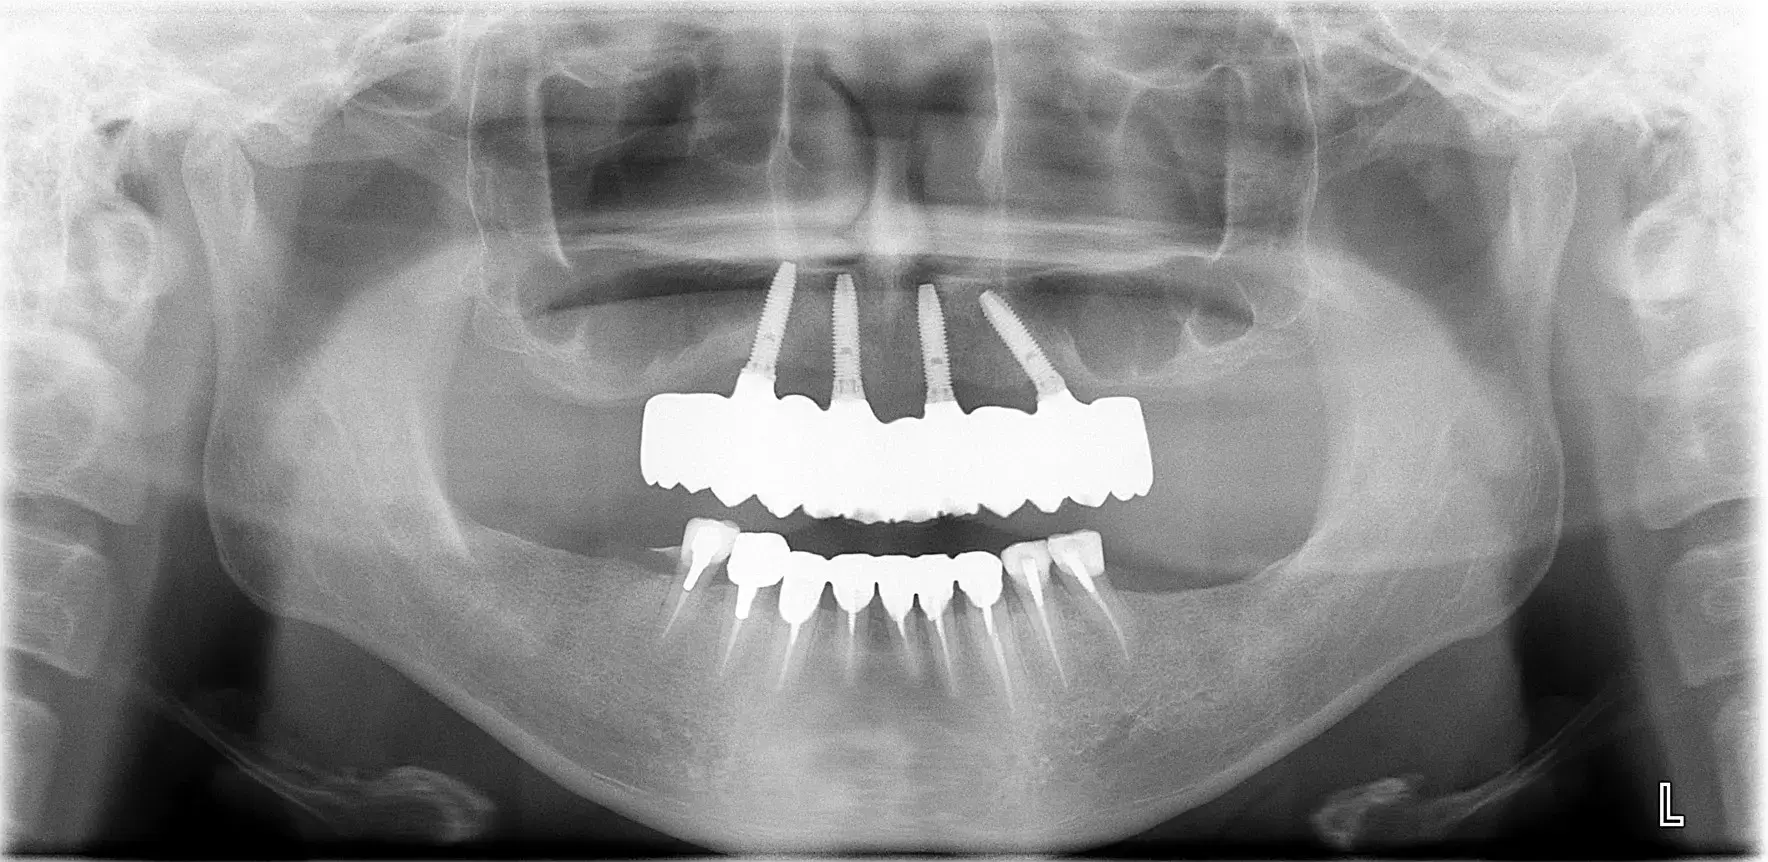

| 治療ケース |

上顎左右サイナスリフトPRP使用 上下顎前歯GBRベニアグラフト,PRP使用 上顎8本12歯インプラント 下顎7本12歯インプラント 上部構造ハイブリッドセラミック(咬合確保・審美歯科) |

| 症状 | 事故により歯を喪失され、体調不良もあり歯科医院への通院ができなかった。 |

| 治療結果 | 咬合を確保した事により、しっかり食事も摂取しやすくなり、体調良好に繋がった。審美的にも改善し見た目も健康になられ、エイジングケアに繋がった。 ※治療結果は患者様によって個人差があります。 |

| 治療方法 | 口腔の健康が全身の健康に繋がることをしっかりとお伝えし残存歯すべて抜歯、前歯部上顎洞に対して大がかりな骨造成を経てインプラント治療により咬合を確保した。 |

| 治療費用(税込) | 上顎左右サイナスリフト:528,000円(税込)

| 治療期間 | 2年 |

| メインテナンスの頻度 | 3ケ月毎 |

| 治療を行う上での注意点(リスク / 副作用) |

骨造成やインプラント外科処置後の腫脹、一時的な内出血が起こる事の可能性をしっかりと説明。しばらく咬合されていなかったので、咬合確保時の顎関節痛がある可能性を伝える。 上部構造、インプラント体の破折予防のため、ナイトガード装着。 インプラント周囲炎予防のため、定期的なメインテナンスの必要性。 |